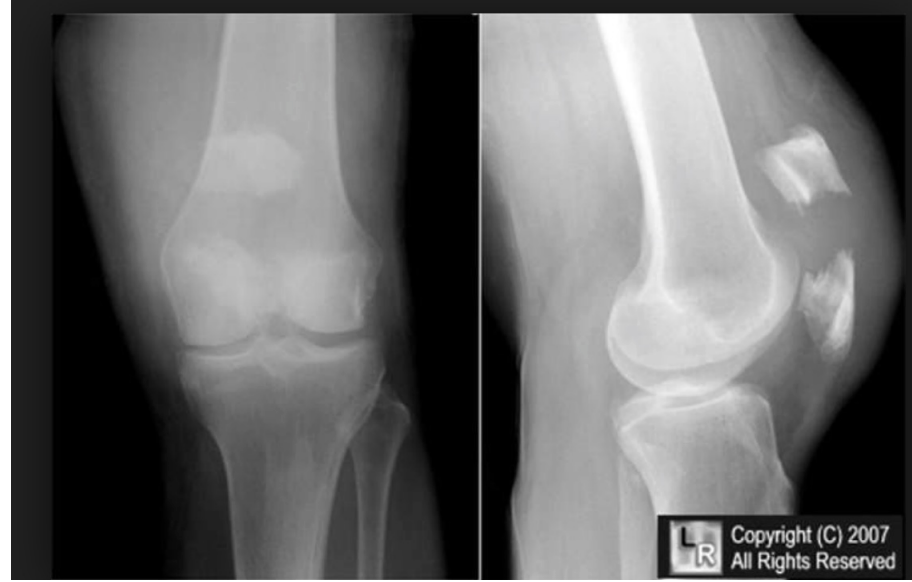

Knee OA

The Evidence- What we know:

obesity affects outcome

interferential current for pain relief

manual therapy plus exercise better than home program

alignment affects pain and disability

psychosocial - self efficacy improves function

adherence - improves long term outcomes

OA Knee

What We Do?

Alignment- Foot wedge, orthotics, bracing if severe

If knee varum, lateral foot wedge

If knee valgum, medial foot wedge